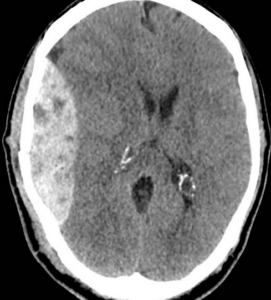

Per ematoma si intende una raccolta di sangue fuoriuscito dal sistema circolatorio e localizzata in un tessuto o in una cavità dell'organismo.

- traumi la cui forza vulnerante agisca su una struttura vascolare (ematomi da sezione diretta di un vaso) o sul tessuto o sull'organo che la contiene (lacerazione indiretta dei vasi come nell'ematoma muscolare, epatico o splenico, nell'ematoma cerebrale);

L'ematoma può interessare ogni struttura corporea e la sua gravità è legata, più che alla grandezza, alla sede in cui si sviluppa: